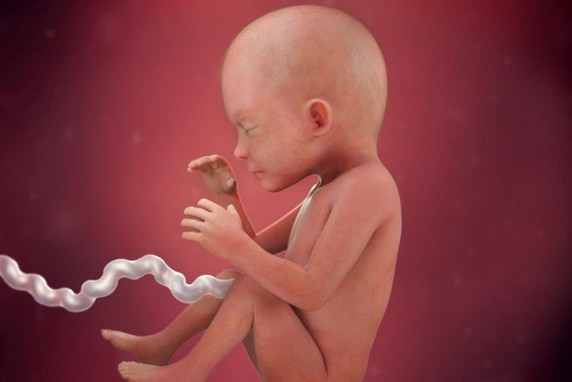

الأسبوع السابع والعشرون

خلال هذا الأسبوع يبدأ شكل الجنين بالوضوح ويصبح قريباً للشكل الذي يظهر به الجنين عند الولادة، ولكن مع اختلاف أنه صغير الحجم كما أ هناك بعض الأعضاء لم يكتمل نموها بعد مثل الرئتين والكبد، جدير بالذكر أن هناك حالات معينة يولد فيها الطفل خلال هذا الأسبوع ويعيش بشكل طبيعي جداً إذا تم الاهتمام والعناية به من قبل الأطباء بعد ولادته.

الأسبوع الثامن والعشرون

تبدأ جفون الطفل بالتفتح وتتشكل رموشه خلال هذا الأسبوع كما يبلغ وزنه 1 كيلو وكذلك يمكن ولادته بهذا الأسبوع وتصبح فرص حياته كبيرة بنسبة تتعدى ال90%.